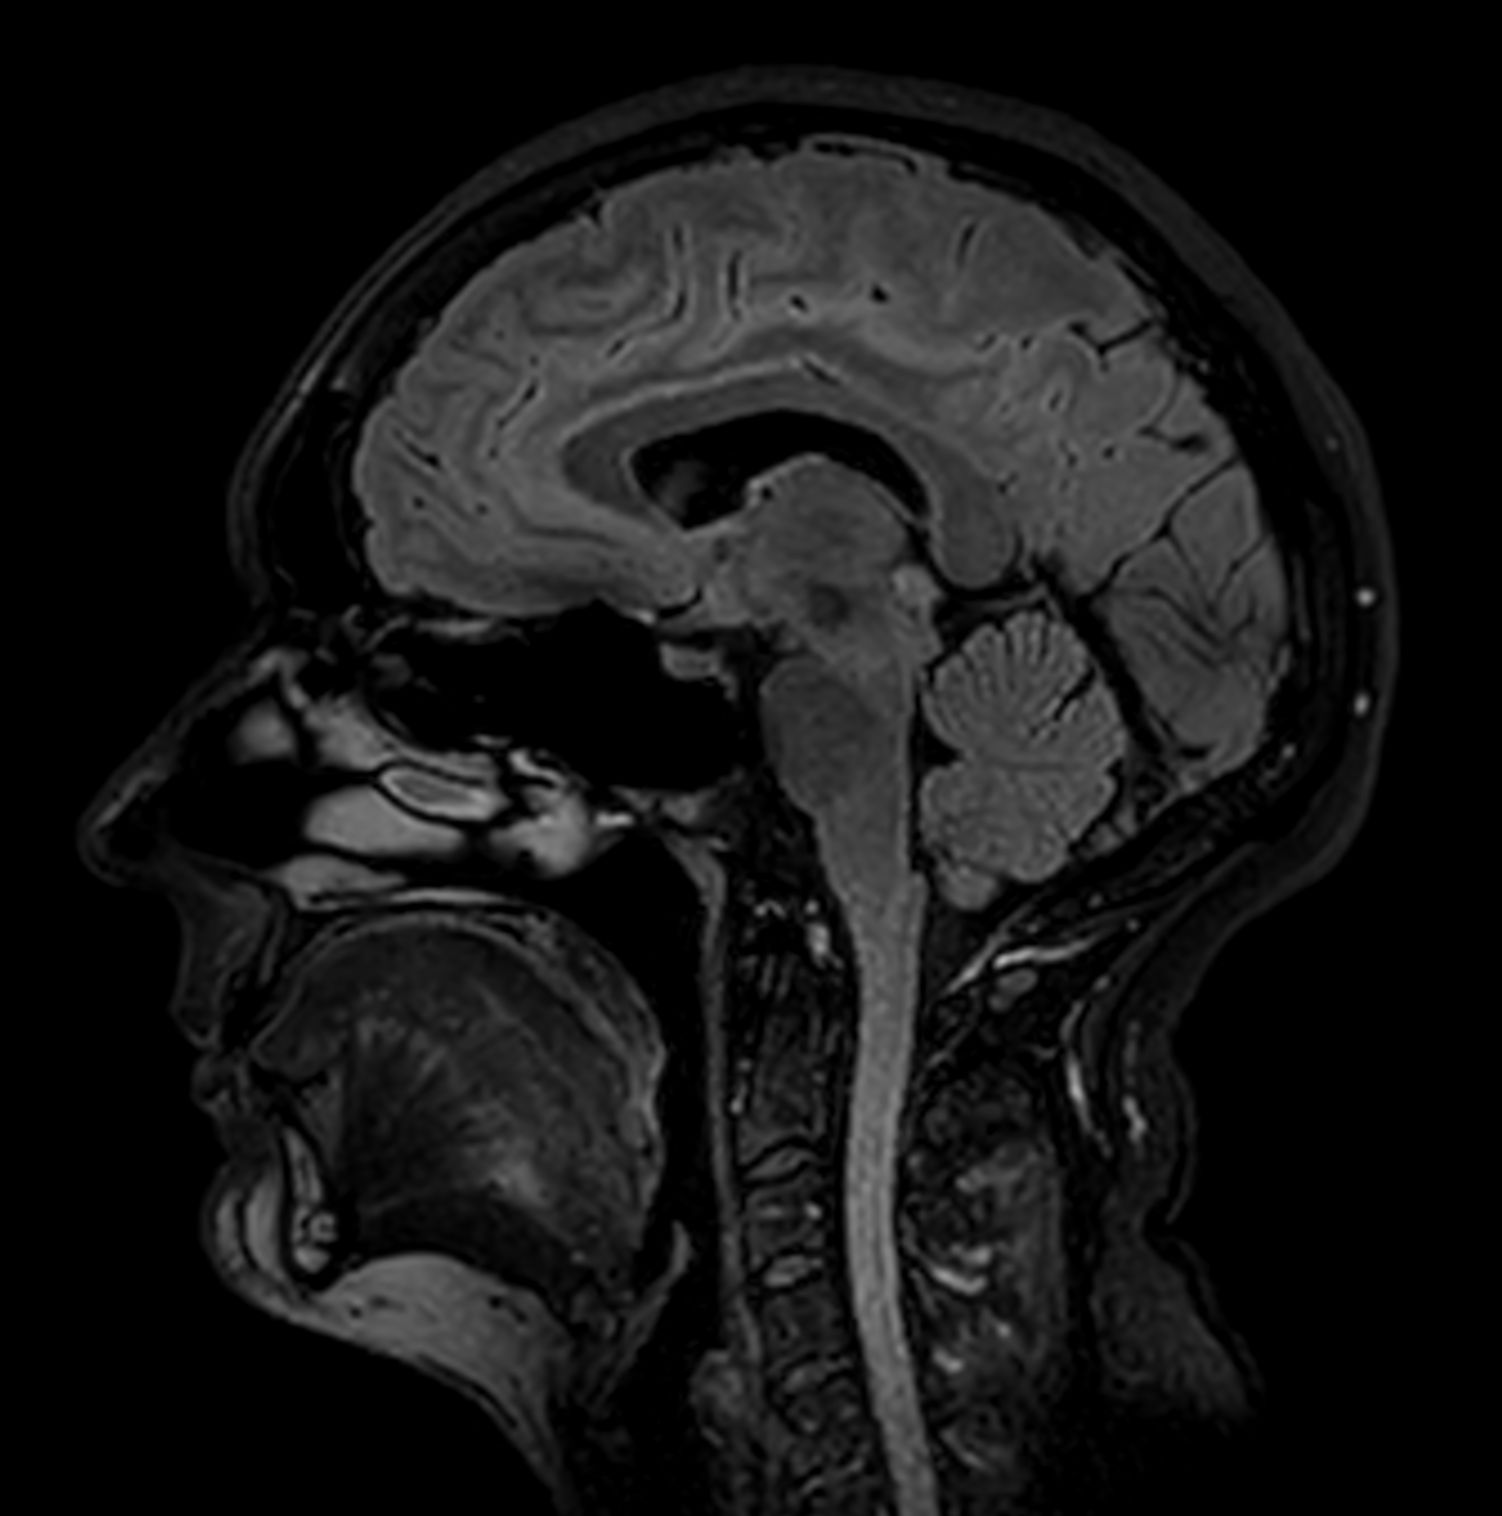

Alzheimer’s Disease Anti-Amyloid Immunotherapies (ARIA) 3.0T

Amyloid clearing medication, such as Aduhelm (Aducanumab) and Leqembi (Lecanemab) have been cleared by the FDA in 2022/2023, to slow down cognitive decline in early-stage Alzheimer’s disease. ASNR-recommendations for AD therapeutic imaging were published in 2022 for eligibility assessment as well as for monitoring for amyloid-related imaging abnormalities. This ExamCard includes ASNR-recommended consensus protocols for imaging of Alzheimer’s Disease Anti-Amyloid Immunotherapies (ARIA). (Cogswell et al., AJNR 2022,43(9)E19-E35;DOI: https://doi.org/10.3174/ajnr.A7586))